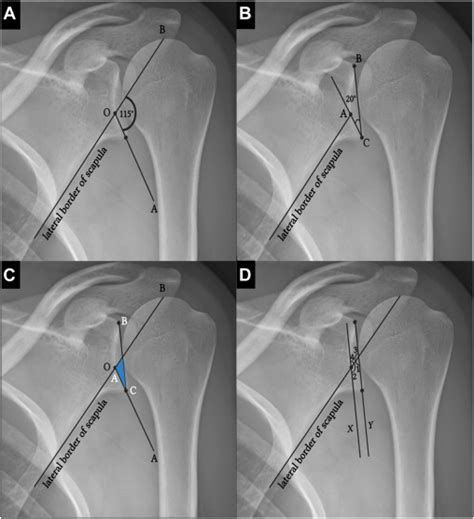

Projection geometry and consistency

Maintaining consistent projection geometry across studies enables meaningful comparisons over time. When projection angles vary, the orientation cues may appear misleading. A standardized protocol for positioning and projection selection supports diagnostic confidence.

Practical Techniques and Common Projections

Understanding typical projections helps technicians achieve reliable orientation in routine studies. For example, frontal views are often aligned with the patient in the same plane, while lateral views add depth cues. In Image Orientation Radiography, documentation of the projection name, patient position, and marker orientation is part of quality control.

Anterior-Posterior and Lateral Views

These classic views form the backbone of many radiographic exams. Ensure the patient is positioned correctly and that the image displays the expected relationships between bones and soft tissues. Orientation cues such as the body midline and marker placement support accurate interpretation.

Special projections and pitfalls

Some studies use oblique or angled projections to visualize structures obscured in standard views. These require careful documentation of the orientation and the reasoning for deviation. Awareness of common misorientation pitfalls helps reduce errors in Image Orientation Radiography.